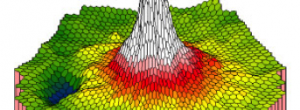

Hyporeflective wedge-shaped band in geographic atrophy secondary to age-related macular degeneration: a little-understood spectral domain optical coherence tomography finding.